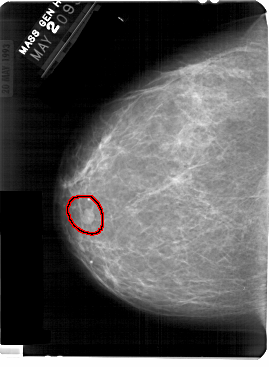

FILE: A_1369_1.LEFT_MLO.OVERLAY

TOTAL_ABNORMALITIES 1

ABNORMALITY 1

LESION_TYPE MASS SHAPE OVAL MARGINS CIRCUMSCRIBED

ASSESSMENT 4

SUBTLETY 5

PATHOLOGY BENIGN

TOTAL_OUTLINES 1

BOUNDARY

FILE: A_1369_1.LEFT_CC.OVERLAY